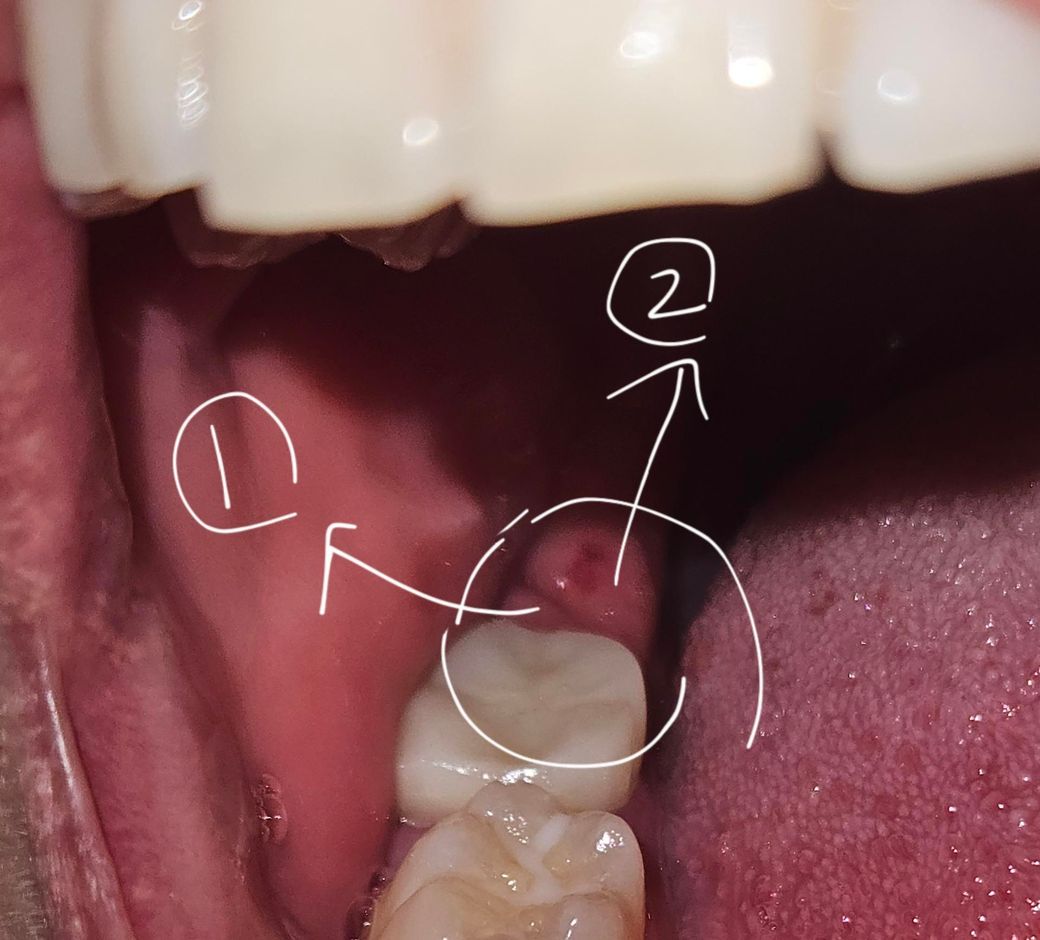

씌우기전에 충치를 제거하기위해 뒤쪽에 걸리적 거리는 잇몸을 태워서 제거했는데 지금 보니까 잇몸이 두갈래로 자라고있는건지 어떤 염증이나 암같은 덩어리가 생긴건지 뭐가 있더라고요.

사진을 첨부하는데 2번은 잇몸이 맞는것같고 1번이 뭔지모를 덩어리입니다. 뭔지 아시는 분 계시면 도움 부탁드립니다. 감사합니다

• 1번 째 사진